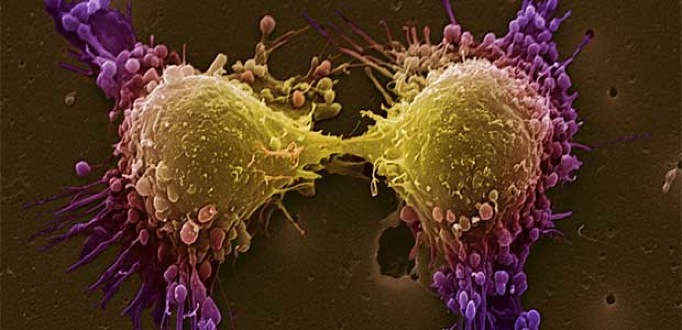

El cáncer de próstata es el tercer tumor más frecuente en los varones y la tercera causa de muerte por cáncer, provocando más de 5.000 fallecimientos cada año en España. Se estima que uno de cada seis varones desarrollará cáncer de próstata a lo largo de su vida.Por fortuna, cada año se realizan más diagnósticos precoces y hemos logrado aumentar la curación y supervivencia.